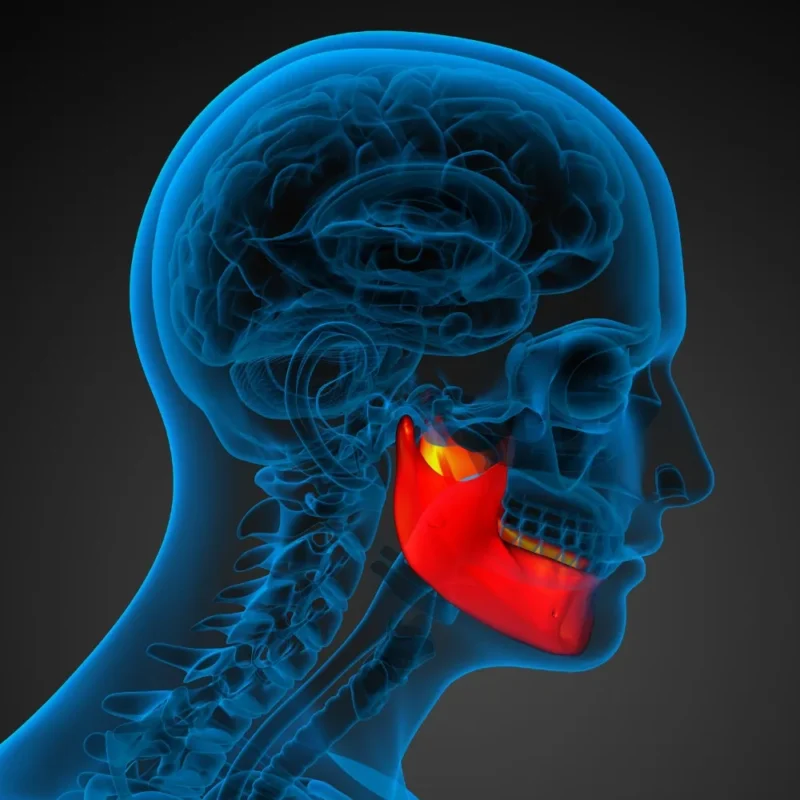

Çene cerrahisi, diş hekimliğinin uzmanlık alanlarından biri olup, çene kemikleri, ağız içi yumuşak dokular, diş kökleri, sinüs bölgesi ve temporomandibular eklem (çene eklemi) gibi yapıları ilgilendiren cerrahi işlemleri kapsar. Gelişen teknoloji ve uzmanlaşmış hekimler sayesinde artık pek çok kompleks vaka çene cerrahisi sayesinde başarıyla tedavi edilebilmektedir. Bu yazıda, hangi durumlarda çene cerrahisi gerektiğini, tedavi sürecini, […]